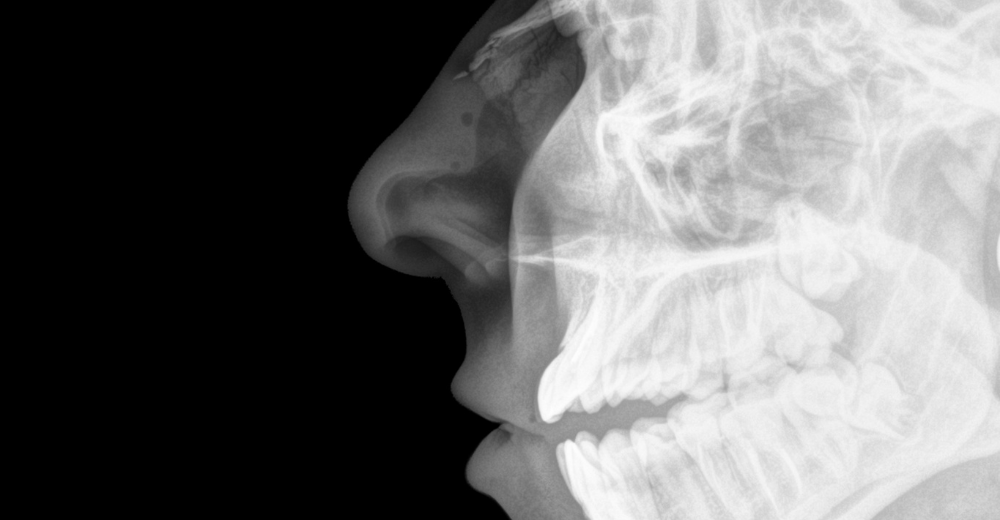

L’abbreviazione RX si riferisce alla radiografia, un metodo di imaging medico che utilizza radiazioni ionizzanti per creare immagini dettagliate delle strutture ossee e dei tessuti interni. L’RX Ossa Nasali si focalizza sulle ossa del naso, fornendo un’immagine chiara e nitida che consente di visualizzare eventuali alterazioni.

L’RX Ossa Nasali è un esame non invasivo che viene effettuato presso il Poliambulatorio S-Medical Group di Sora e si avvale di una quantità minima di radiazioni per ottenere immagini delle ossa nasali. Questo esame è particolarmente utile per individuare lesioni traumatiche, come fratture o dislocazioni, nonché per valutare deviazioni del setto nasale, sinusiti croniche o la presenza di polipi.

Cosa si Osserva con un RX Ossa Nasali?

L’RX Ossa Nasali permette di visualizzare chiaramente le ossa del naso e le loro eventuali anomalie strutturali. Questo esame risulta particolarmente efficace per:

• Identificare Fratture: L’RX evidenzia eventuali linee di frattura e scomposizioni ossee.

• Valutare il Setto Nasale: Consente di osservare deviazioni che potrebbero ostacolare la respirazione corretta.

• Diagnosticare Sinusiti: Rileva accumuli di liquidi o infiammazioni nei seni nasali.

• Individuare Polipi o Masse: Consente di osservare la presenza di eventuali formazioni anomale.